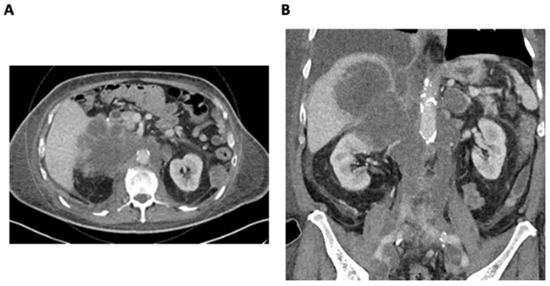

2. Detailed Case Description